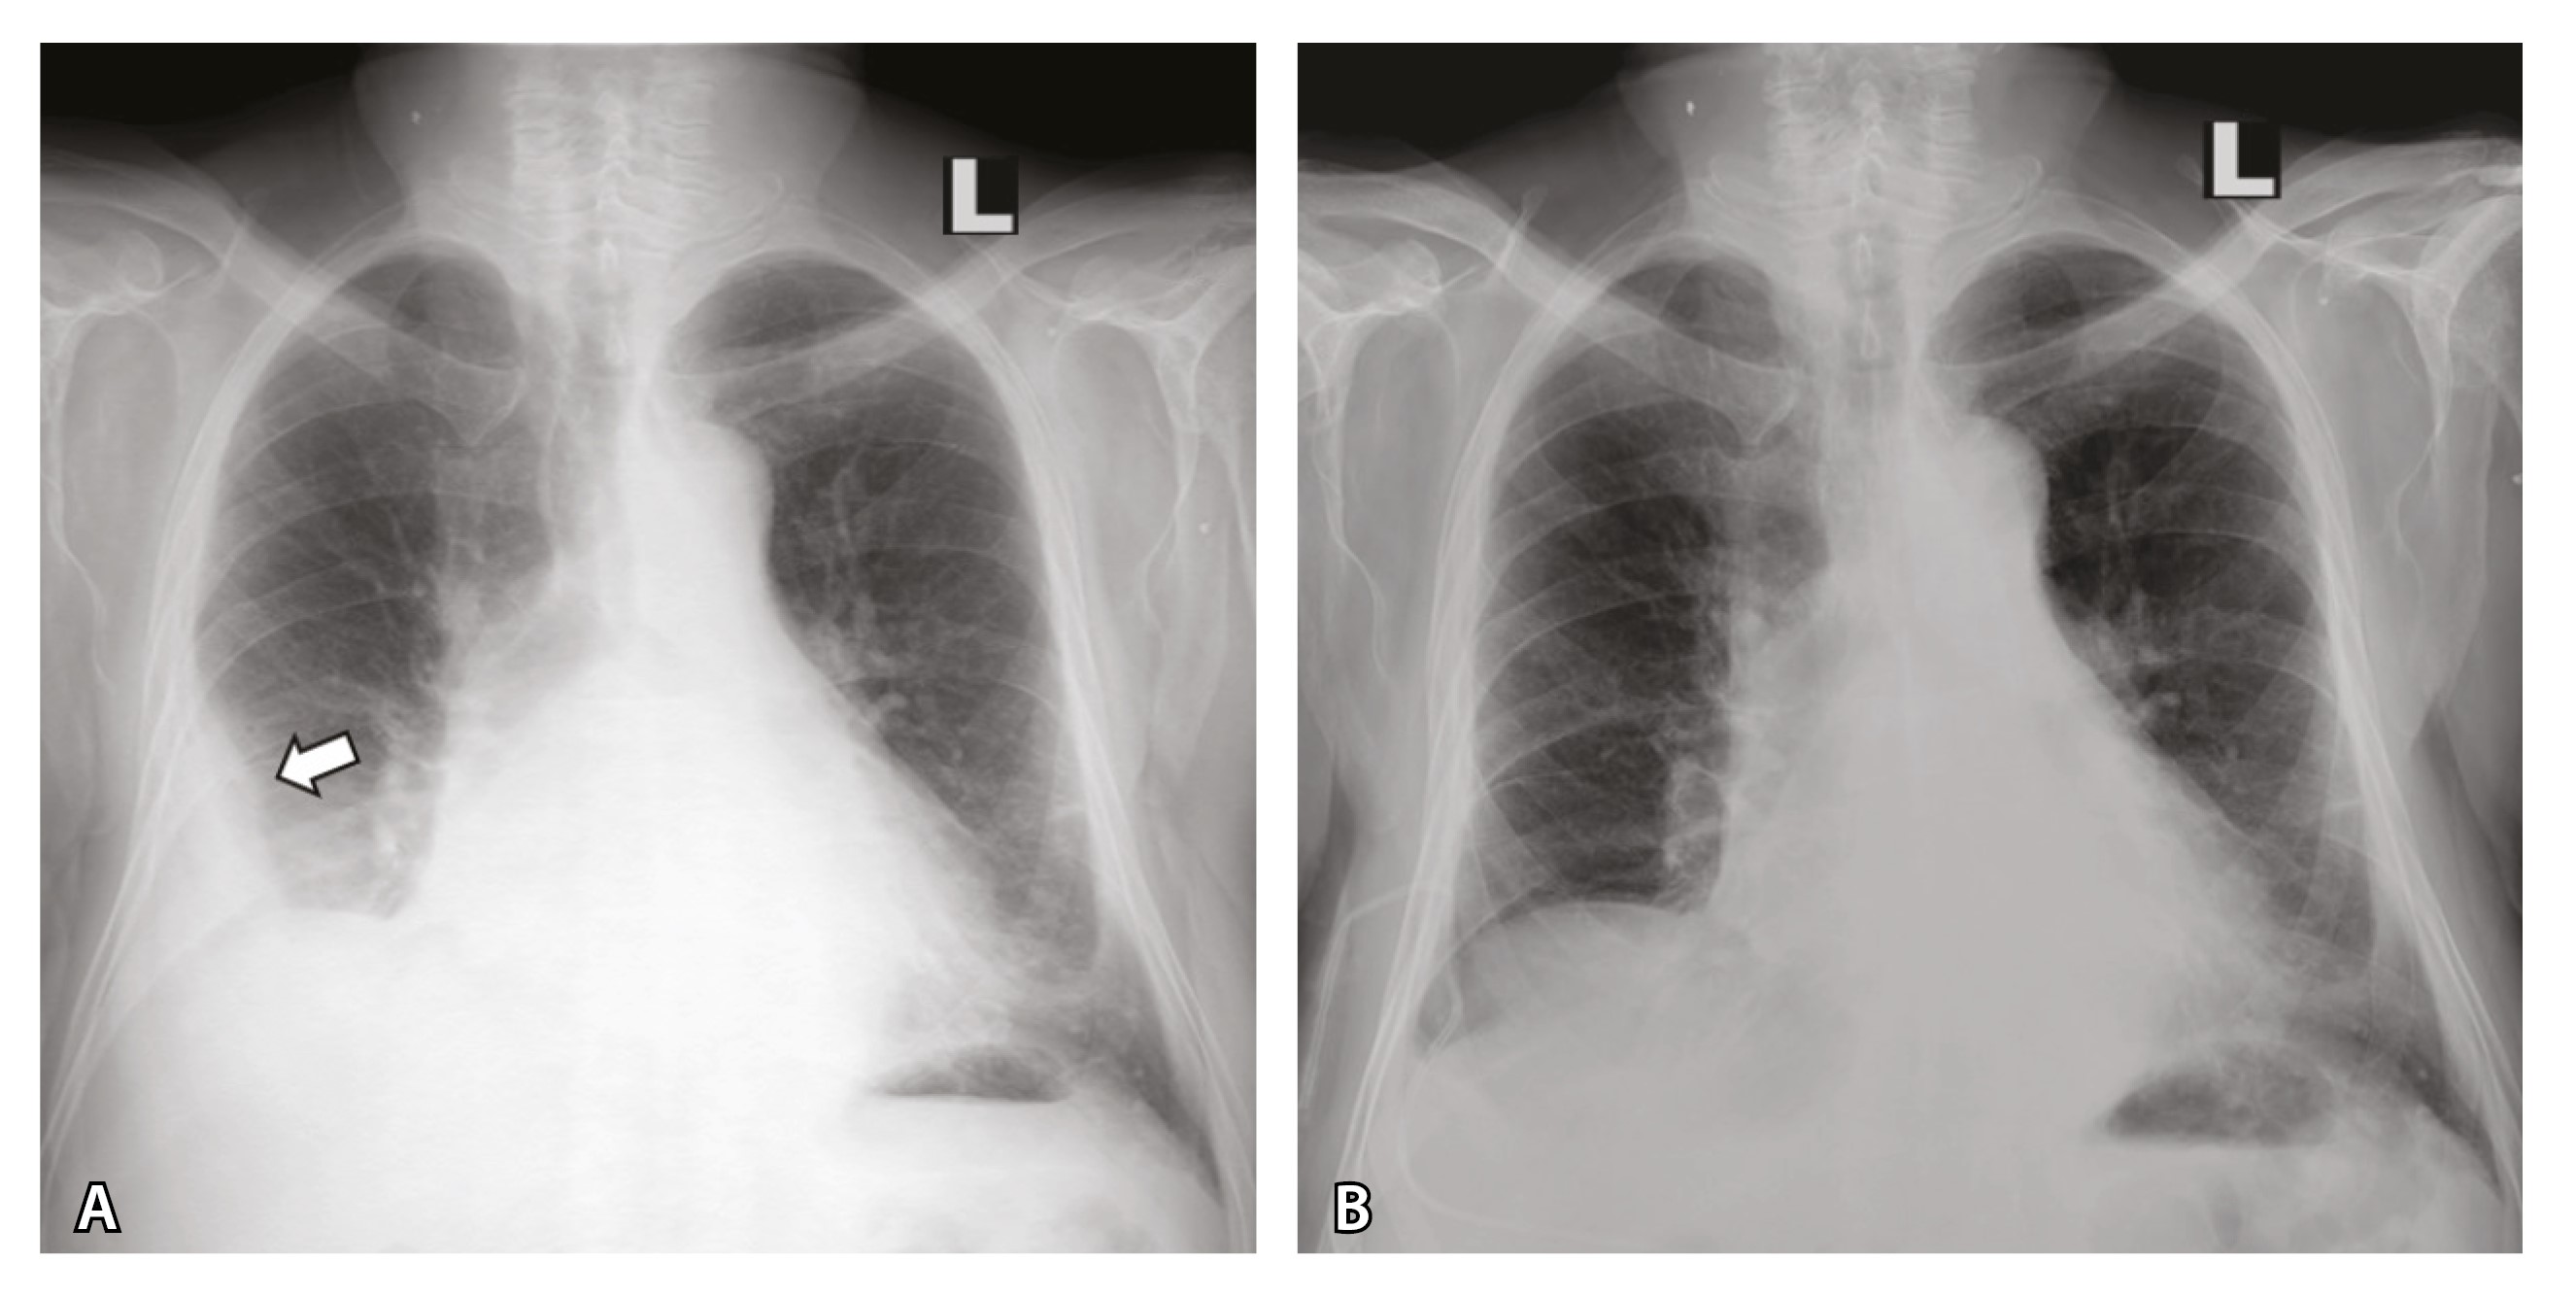

За 2 года существования лимфаденопатии средостения (КТ ОГК за это время выполнена 7 раз, рис. 4) и неспецифических изменений в периферической крови диагноз установлен не был, несмотря на обращение к онкологу.

Рис. 4. Серия КТ-изображений, отражающая длительность существования внутригрудной лимфаденопатии. В верхних рядах изображений – аксиальные срезы на уровне пакета лимфатических узлов в верхнем средостении (размер обозначен желтым маркером), в нижних – срезы, отражающие состояние перикарда. Белой стрелкой отмечена жидкость в правой плевральной полости, белым треугольником – накопление жидкости в полости перикарда в марте 2024 г.